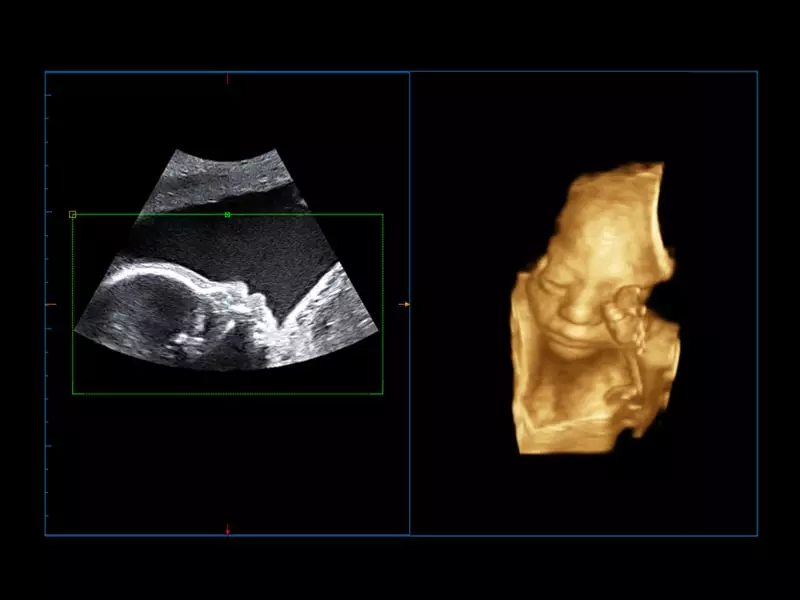

MyLab™C25 - Baby face

MyLab™C25 - Baby face

MyLab™E80 - 3D - Baby Face

MyLab™E80 - 3D - Baby Face

MyLab™9 Platform - Real-time baby face with 4D imaging

MyLab™9 Platform - Real-time baby face with 4D imaging

MyLab™9 Platform - Baby Face rendering in real-time with XLight

MyLab™9 Platform - Baby Face rendering in real-time with XLight

MyLab™A50 - Face profile

MyLab™A50 - Face profile

MyLab™A70 - Baby face

MyLab™A70 - Baby face